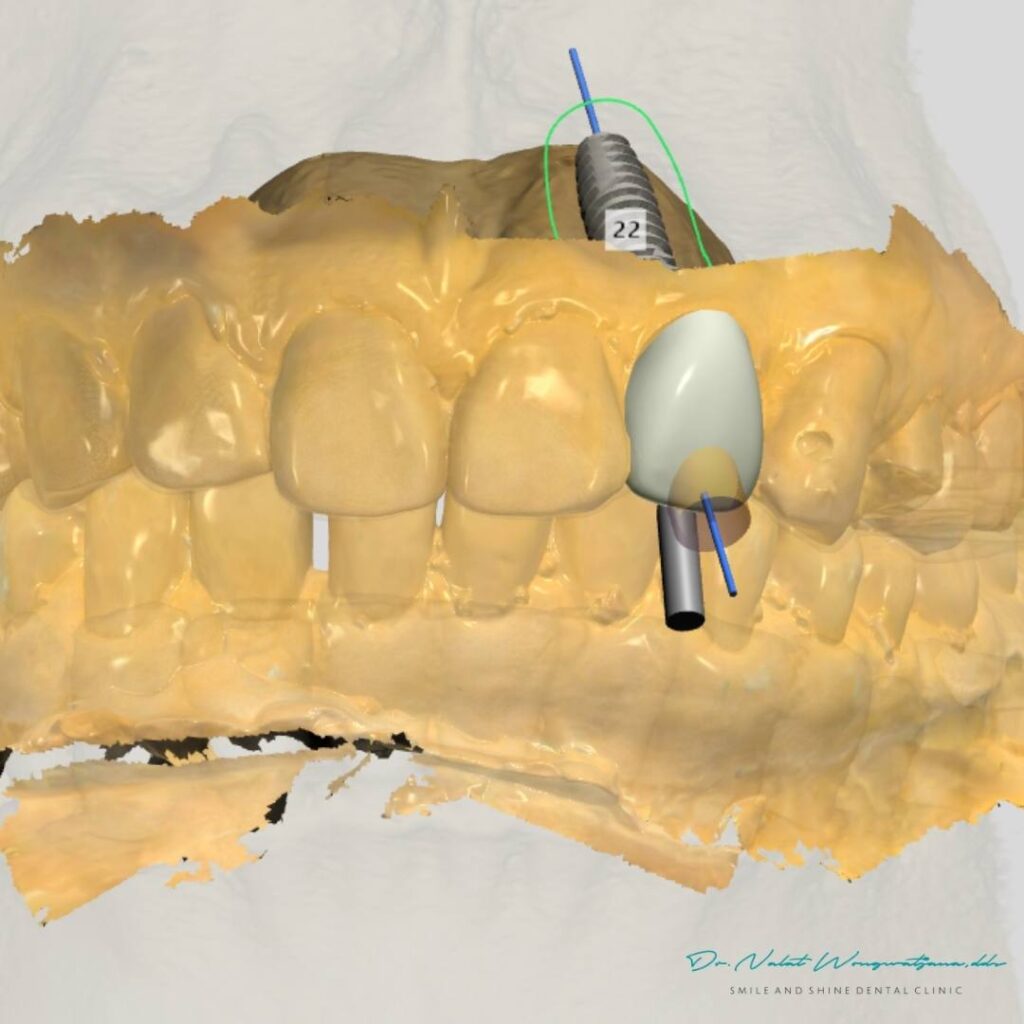

หนึ่งในข้อดีของ Computer Guided Implant (Static Guide)

คือการวางแผนตำแหน่งรากฟันเทียมแบบดิจิทัลล่วงหน้า

ทันตแพทย์สามารถ

- ออกแบบตำแหน่งรากฟัน

- ออกแบบรูปทรงฟัน

- และผลิตฟันชั่วคราวเตรียมไว้ก่อนผ่าตัด

Digital planning ทำให้ตำแหน่งรากสัมพันธ์กับฟันในอนาคตตั้งแต่ต้น